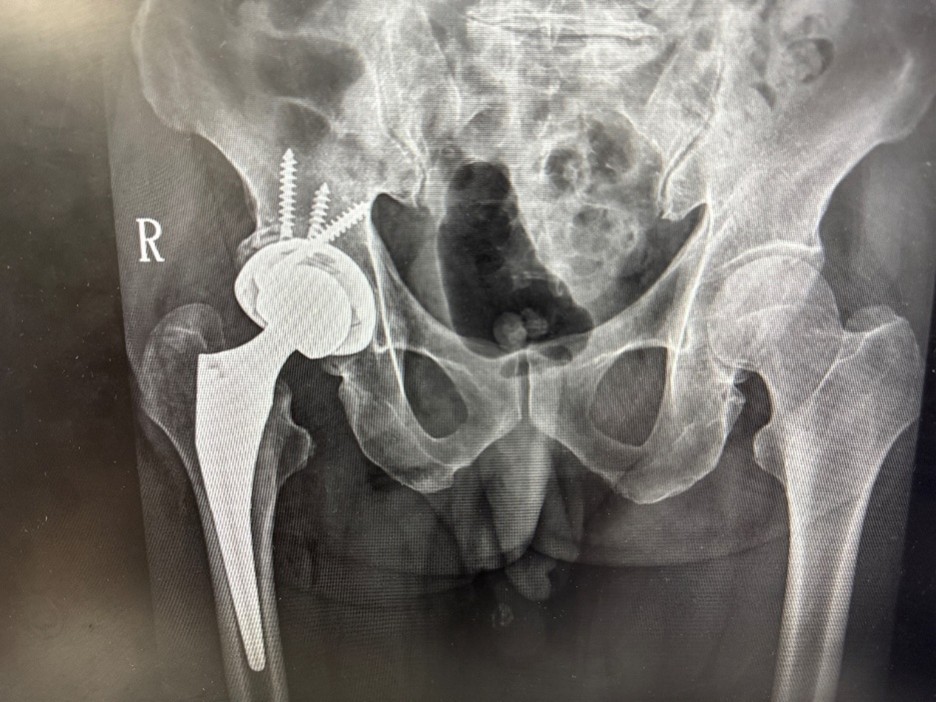

76歲男性病人多年前因髖臼骨折接受手術,術後留下垂足(foot drop)與步態異常,長期行動不便,導致外傷性退化性髖關節炎,連如廁與行走都成為挑戰。經新竹臺大分院骨科團隊詳細評估並與病人充分溝通後,決定採用「前側入路(Direct Anterior Approach, DAA)」人工髖關節置換手術,避開之前的手術區域,病人術後當天即可床邊如廁並下床行走,疼痛顯著減輕,展現微創技術在高齡手術中的安全與高效,成功改善長年困擾。

新竹臺大分院骨科部主任賈維焯醫師指出:「DAA手術的最大優勢在於保留肌肉結構、縮小傷口並降低疼痛,使病人能於術後儘早下床活動,加速恢復日常生活功能。」他也說,「看到病人術後能自在行走、重拾生活自信,是團隊推動微創精準醫療的最大動力。」

賈維焯主任說明,DAA人工髖關節置換術是近年國際間發展成熟的微創技術。新竹臺大分院骨科團隊結合術前影像分析與精準定位系統,提高手術植入穩定性與下肢長短對位準確性。與傳統後側入路手術相比,DAA術式不僅可減少術後疼痛與出血,亦能縮短復健期並降低脫臼風險。